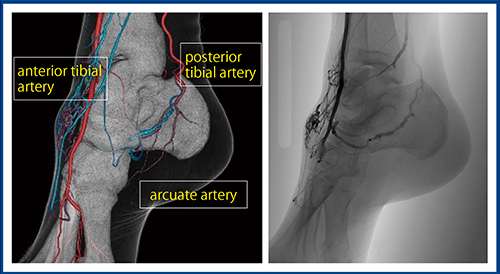

症例4は50歳代,男性,足背動脈の高流速動静脈奇形である。Aquilion PrecisionのSHRモードで撮影した術前CTにて,まず異常血管塊(nidus)と流入動脈(feeder),流出静脈(drainer)の位置関係を把握する。さらに重要なのは,足先の血管の性状や前脛骨動脈と後脛骨動脈の交通など,また,足底動脈の状態を把握することである(図4)。血管塞栓時に塞栓物質による遠位塞栓の可能性があるため,血管走行を術前に十分に把握することでより安全な治療が可能となる。

図4 症例4:足背動脈の高流速動静脈奇形における血管塞栓術前の評価